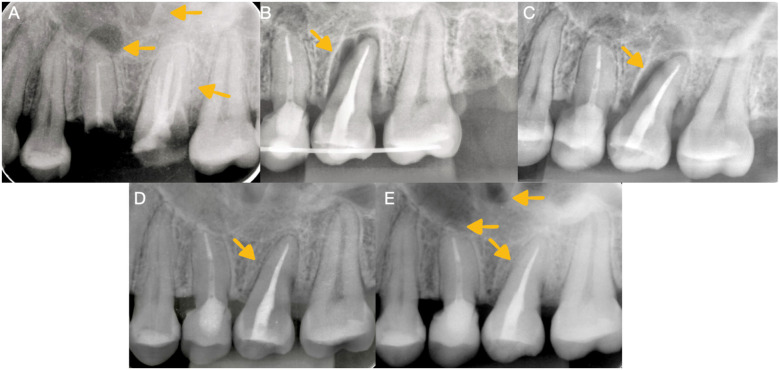

本病例报告介绍了牙齿自体移植的使用,这是一种将供体牙齿转移到同一患者的受体部位的手术,改善了功能和美学特征。与传统的修复和外科治疗(如牙种植)相比,该技术的优点被讨论。患者27岁,无相关病史,因牙髓治疗和牙源性鼻窦炎导致的骨折牙疼痛和不适进行评估。诊断出不可修复的上颌第一磨牙并拔出并替换为先前经根管治疗的上颌第三磨牙,使用3d打印复制品重塑牙槽部位。干预是成功的,之后进行了充分的临床和影像学随访3年,显示良好的骨形成和牙周韧带的连续性,没有病理性吸收的迹象。这个案例表明,如果计划和执行得当,牙齿自体移植可以成为一种有效的、生物的牙齿康复替代方法,特别是使用先进的技术,如锥体束计算机断层扫描和3d打印供牙复制品。

This case report presents the use of dental autotransplantation, a procedure in which a donor tooth is transferred to a recipient site in the same patient, improving functional and esthetic characteristics. The advantages of this technique compared to conventional prostheses and surgical treatments, such as dental implants, are discussed. A 27-year-old patient with no relevant medical history was evaluated for pain and discomfort in fractured teeth with previous endodontic treatments and odontogenic sinusitis. A non-restorable maxillary first molar was diagnosed and extracted and replaced with a previously endodontically treated maxillary third molar, for which a 3D-printed replica was used to reshape the alveolar site. The intervention was successful, after which an adequate clinical and radiographic follow-up was carried out for 3 years, showing good bone formation and continuity of the periodontal ligament, with no signs of pathological resorption. This case demonstrates that, when properly planned and executed, dental autotransplantation can be an effective and biological alternative for dental rehabilitation, especially with the use of advanced technologies, such as cone beam computed tomography and 3D-printed replicas of donor teeth.